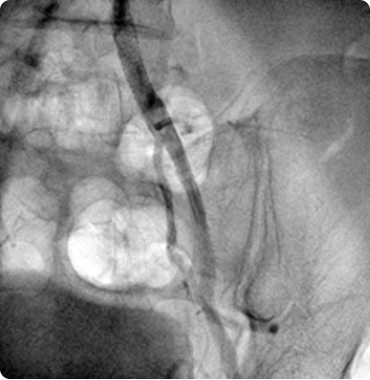

Interesting Cases